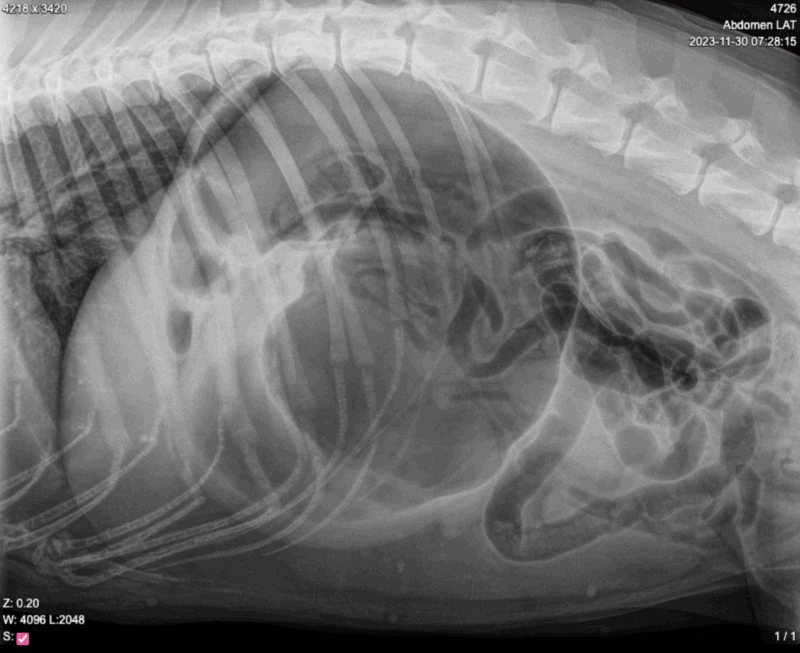

Koiran mahalaukun kiertymä (GDV) on tila, jossa koiran mahalaukku täyttyy ensin kaasulla ja nestillä, ja sitten kiertyy itsensä ympäri. Tämä akuutti hätätila estää veren virtauksen mahalaukkuun ja muihin elimiin sekä estää kaasujen poistumisen, mikä johtaa nopeasti henkeä uhkaavaan tilanteeseen.

Vatsan turpoaminen on toinen keskeinen ja näkyvä oire. Koiran vatsa alkaa laajentua, erityisesti kylkiluiden takaa. Vatsa voi tuntua pingottuneelta, kovalta ja kivuliaalta kosketettaessa. Koira saattaa reagoida voimakkaasti vatsaan koskettaessa tai jopa vinkaista kivusta.

Alun levottomuus ja epämukavuus voivat kehittyä vakaviksi hengitysvaikeuksiksi. Koira läähättää voimakkaasti ja hengitys muuttuu pinnalliseksi ja nopeaksi. Tämä johtuu siitä, että laajentunut mahalaukku painaa palleaa ja keuhkoja, vaikeuttaen normaalia hengitystä. Samalla koiran sydämen syke nopeutuu huomattavasti, kun elimistö yrittää kompensoida verenkierron heikkenemistä.

Tilan edetessä koiralle kehittyy sokin oireita. Koira muuttuu heikoksi, voi horjua tai jopa kaatua. Se saattaa olla haluton liikkumaan tai reagoimaan ympäristöönsä. Vakavassa tapauksessa koira voi menettää tajuntansa. Vatsaontelon paine lisääntyy entisestään, mikä voi johtaa mahalaukun repeämiseen.